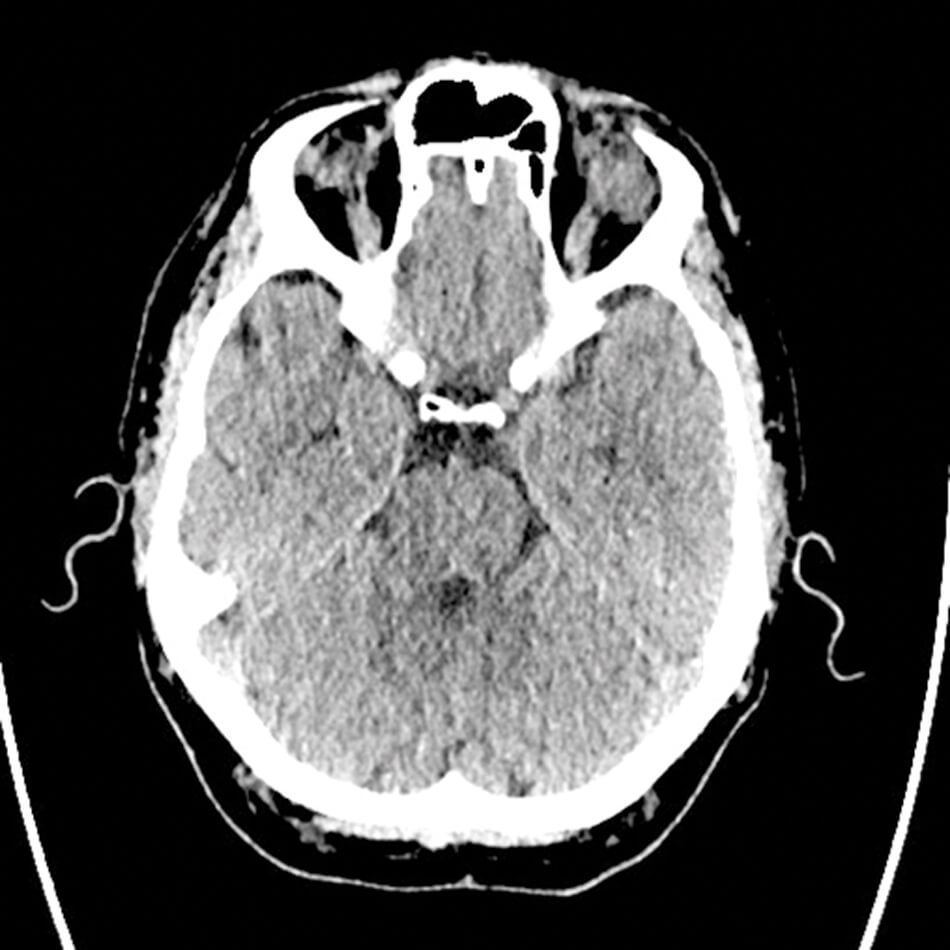

Figure 1: CT scan of head.

A CT head was requested which showed an 18mm contrast enhancing lesion superior and lateral to the left eye globe. This seemed to involve the superior and lateral rectus muscles along with mass effect over the left globe and possible orbital inflammation.